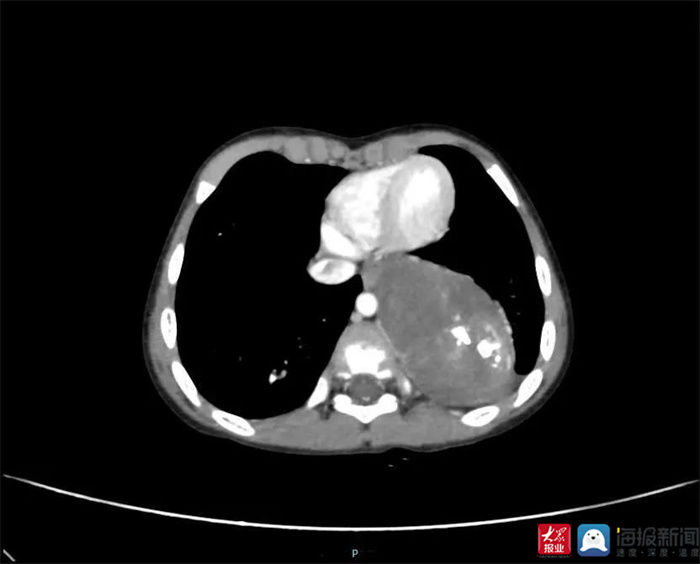

4岁多的可爱男孩远远(化名)是泰安市中心医院儿童外科的一名患儿,本应该是天真烂漫的年纪,却因咳嗽多日来医院儿内科就诊,经肺CT检查显示:纵膈巨大占位,遂进入儿童外科住院等待进一步检查治疗。

肺CT检查(李庆浩 供图)

远远住院后,儿童外科医师立即给他完善各项相关检查,胸部MRI平扫结果显示肿物与周围器官组织联系紧密。